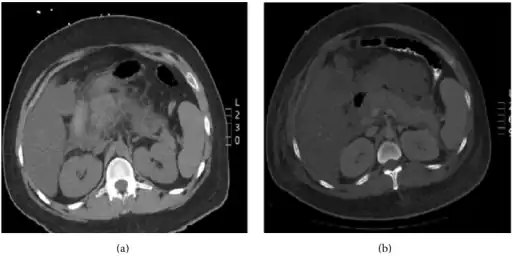

Pegaspargase induced hypertriglyceridemia a) Enlarged pancreas with peripancreatic inflammation b) Interval worsening of acute pancreatitis